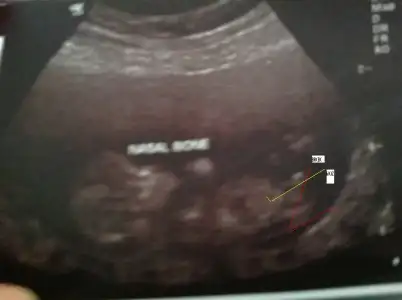

kızlar merhaba benim bebeğimin ultrasonunada bakarmısınız:26::26::26::26::26::26::26::26::26::26::26::26::26::26::26::26::26::26: $ultrason.webp burda 13+5